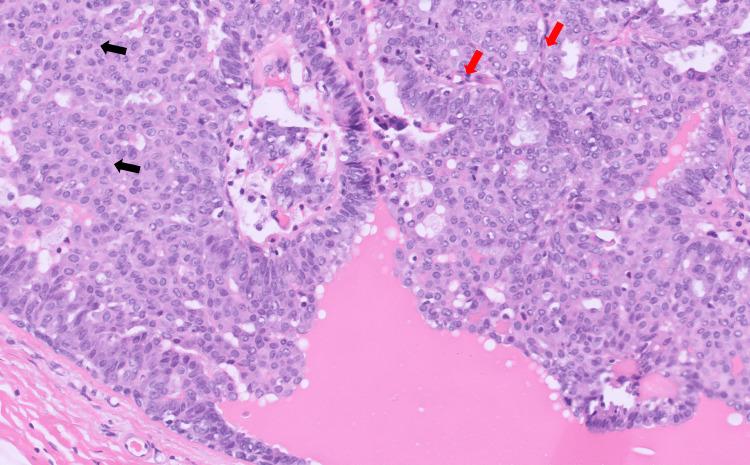

Intraductal papillomas (IDPs) are benign tumors found within breast ducts. Clinicians should be familiar with IDPs given their association with atypical and neoplastic lesions. In our case, the patient was initially diagnosed with and treated for an abscess given clinical symptoms of breast pain, erythema, and swelling, but upon returning to the clinic a year later due to persistent symptoms, she was found to have an IDP. This case underscores the importance of atypical imaging features and close follow-up when evaluating breast lesions.

导管内乳头状瘤(IDP)是在乳腺导管内发现的良性肿瘤。鉴于其与非典型性和肿瘤性病变的关联,临床医生应熟悉IDP。在我们的病例中,患者最初因乳房疼痛、红斑和肿胀等临床症状被诊断为脓肿并接受治疗,但一年后因症状持续回到诊所时,发现患有IDP。该病例强调了评估乳腺病变时非典型影像学特征和密切随访的重要性。